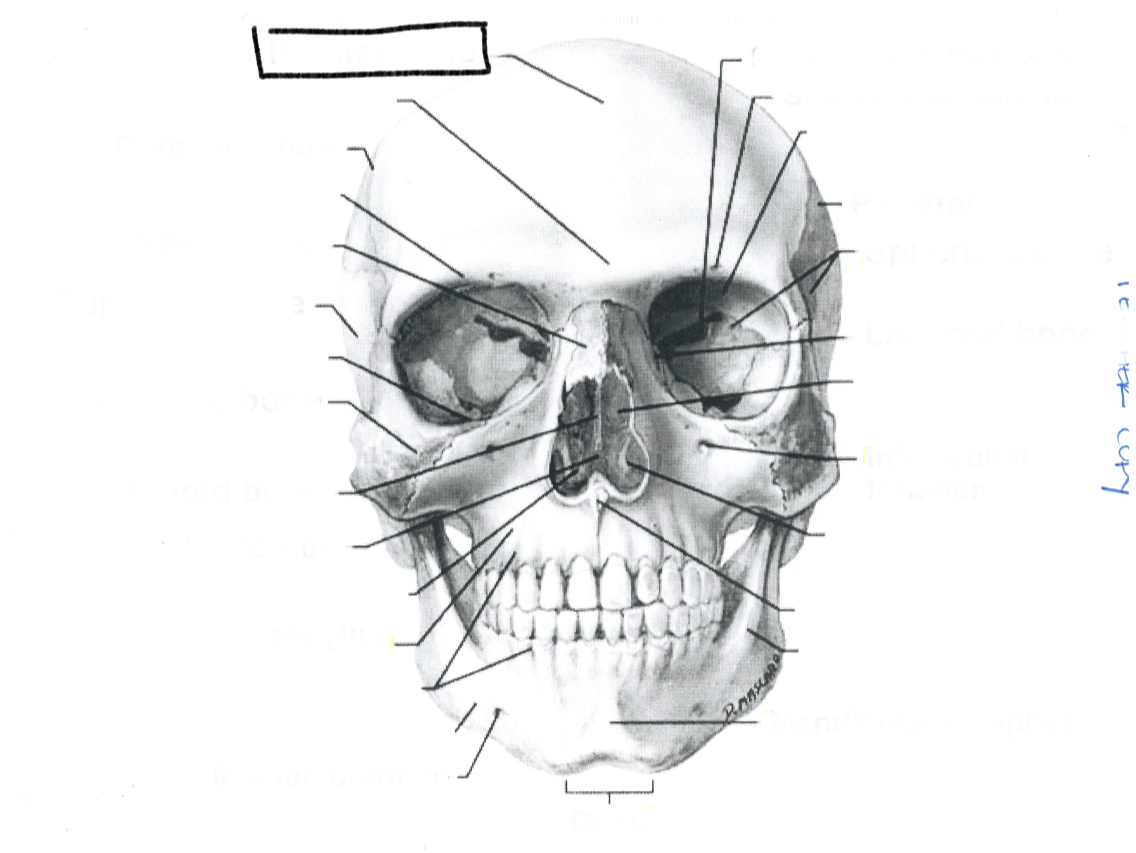

Frontal bone

What is this?

Coronal suture

What is this?

Frontal bone

What is this?

Supraorbital foramen

What is this?

Sphenoid

What is this?

Frontonasal suture

What is this?

Nasal bone

What is this?

Lacrimal bone

What is this?

Ethmoid

What is this?

Maxilla

What is this?

Zygomatic bone

What is this?

Mental foramen

What is this?

Mandible